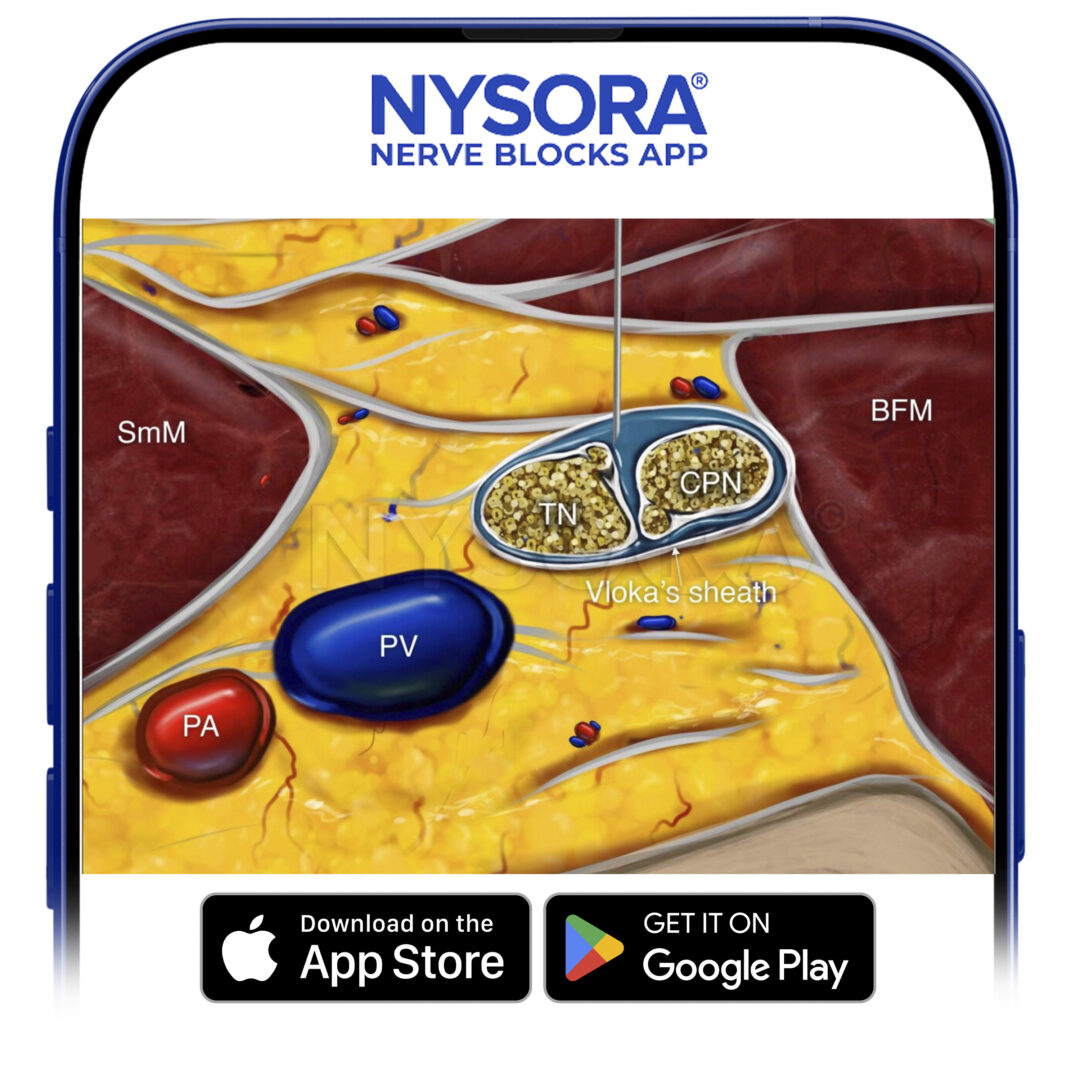

The anatomy of the sciatic nerve in the popliteal fossa is variable, and the division into the tibial nerve (TN) and common peroneal nerve (CPN) occurs at an inconstant distance from the popliteal crease (Figure 1). With nerve stimulator–based techniques, larger volumes (eg, > 40 mL) of local anesthetic have been used to increase the chance of nerve block success.

FIGURE 1. Cross-sectional anatomy of the sciatic nerve in the popliteal fossa. Shown are the common peroneal nerve (CPN), tibial nerve (TN), popliteal artery (PA), popliteal vein (PV), femur, biceps femoris muscle (BFM), semimembranosus muscle (SmM), and semitendinosus (StM) muscle.

The injection of local anesthetic must occur within the sciatic nerve sheath that contains both components of the nerve. The injection is ideally accomplished at the position where both components of the nerve are within the sheath but slightly separated by adipose tissue, allowing for safe placement of the needle between them. Although the sciatic nerve block can be accomplished with an injection around either nerve component, injecting into the space between both is more common in clinical practice.

• Ultrasound imaging should specifically focus on identifying the sciatic nerve sheath (Vloka’s sheath) containing both components of the sciatic nerve (tibial and common peroneal nerves). Successful injection will deposit local anesthetic within the Vloka’s sheath

The goal is to inject the local anesthetic within the common connective tissue (Vloka’s) sheath that envelops the TN and CPN. Alternatively, separate nerve blocks of TN and CPN can be performed.

Reverse Ultrasound Anatomy for a popliteal sciatic nerve block with needle insertion in-plane and out-of-plane and local anesthetic spread (blue). TN, tibial nerve; CPN, common peroneal nerve; PV, popliteal vein; PA, popliteal artery; SmM, semimembranosus muscle; BFM, biceps femoris muscle.